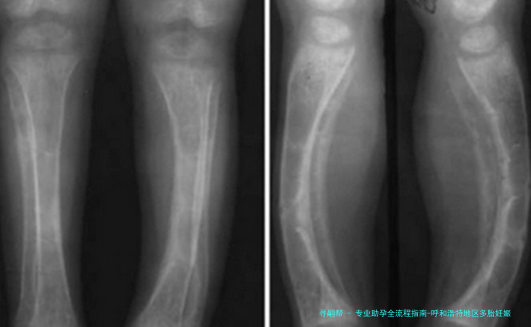

对胎儿来说,多个胎儿妊娠明显增加流产风险(提高5-10倍),导致低出生体重、发育迟缓等问题的发生率明显增高。早产儿各器官发育未成熟,易出现呼吸窘迫综合征、新生儿颅内部出血等多种并发症, *** 妊娠早产儿的死亡率约为单胞胎未足月产儿的2-12倍。